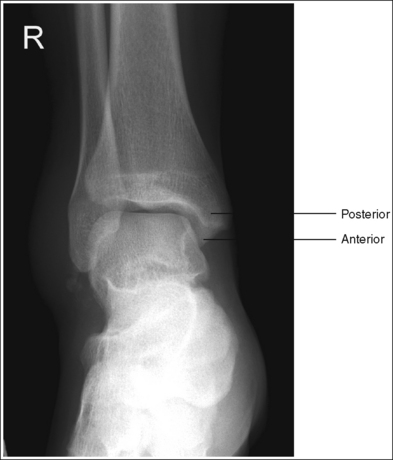

• Evaluating the openness of the tibiotalar joint. On an AP ankle projection, determine whether an open joint was obtained and whether the tibia is demonstrated without foreshortening by evaluating the anterior and posterior margins of the distal tibia. On an AP ankle projection with accurate positioning, the anterior margin is demonstrated approximately 0.125 inch (3 mm) proximally to the posterior margin (see Figure 6-48). If the proximal lower leg was elevated or the central ray was centered proximal to the tibiotalar joint, the anterior tibial margin is projected distally, resulting in a narrowed or obscured tibiotalar joint space (see Image 34). If the distal lower leg was elevated or the central ray was centered distal to the tibiotalar joint, the anterior tibial margin is projected more proximally to the posterior margin than on an AP ankle projection, expanding the tibiotalar joint space and demonstrating the tibial articulating surface (see Image 35).

IMAGE 34

IMAGE 35

• Evaluating the openness of the tibiotalar joint. On an AP oblique ankle projection, you can determine whether the positioning and central ray alignment goals have been met by evaluating the anterior and posterior margins of the distal tibia. On an AP oblique ankle projection with accurate positioning, the anterior margin should be visualized approximately 0.125 inch (3 mm) proximal to the posterior margin. If the proximal lower leg was elevated or the central ray was centered proximal to the tibiotalar joint, the anterior tibial margin is projected distally, resulting in a narrowed or obscured tibiotalar joint. If the patient's distal lower leg was elevated or the central ray was centered distal to the tibiotalar joint, the anterior tibial margin is projected too far proximal to the posterior margin, expanding the tibiotalar joint space and demonstrating the tibial articulating surface (see Images 39 and 40).

The tibiotalar joint space is expanded. The anterior tibial margin has been projected proximal to the posterior margin, and the tibial articulating surface is demonstrated. Either the distal tibia was elevated or the central ray was centered distal to the tibiotalar joint.